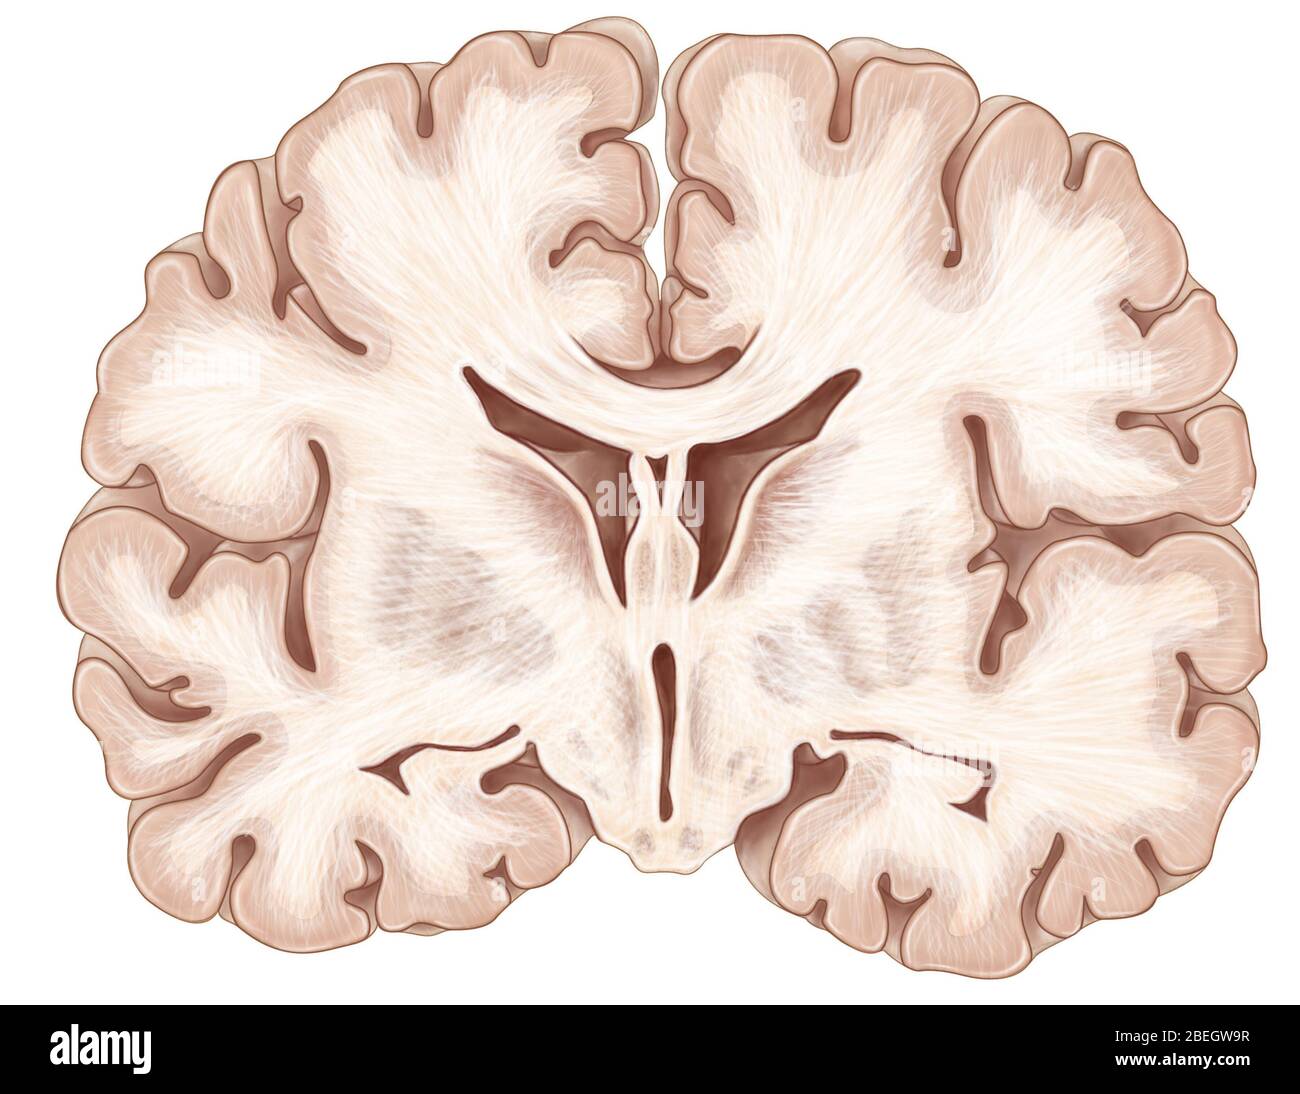

RF3CPM9D1–Abbildung des menschlichen Gehirns mit farbigen Ventrikeln: Lateral (gelb), dritter (orange), vierter (blau), interventrikuläres Foramen (grün), cerebral

RF3CPM9CD–Abbildung des menschlichen Gehirns mit farbigen Ventrikeln: Lateral (gelb), dritter (orange), vierter (blau), interventrikuläres Foramen (grün), cerebral